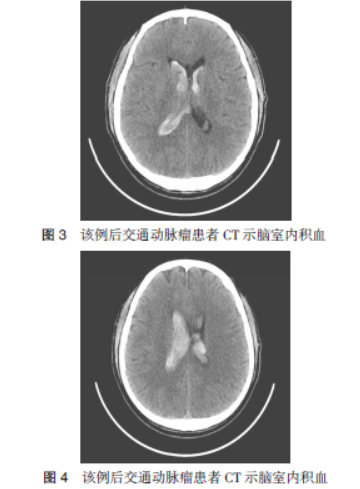

以颞叶出血并破入脑室为首发CT表现的后交通动脉瘤一例并文献复习

病史摘要:男性患者,因突发头痛、头晕2天入院,自服药物症状未改善。既往有糖尿病及冠心病史。诊疗过程:入院查体神志清、颈部稍抵抗等。头部CT示脑出血破入脑室,CT动脉造影显示右侧后交通动脉瘤。家属同意后于入院第3天手术,术中放置脑室外引流,夹闭瘤颈及后交通动脉,术后给予预防血管痉挛、感染等治疗,住院17天出院,随访3个月恢复良好。情况总结:该病例的主要价值在于以颞叶出血并破

动脉瘤

疑难